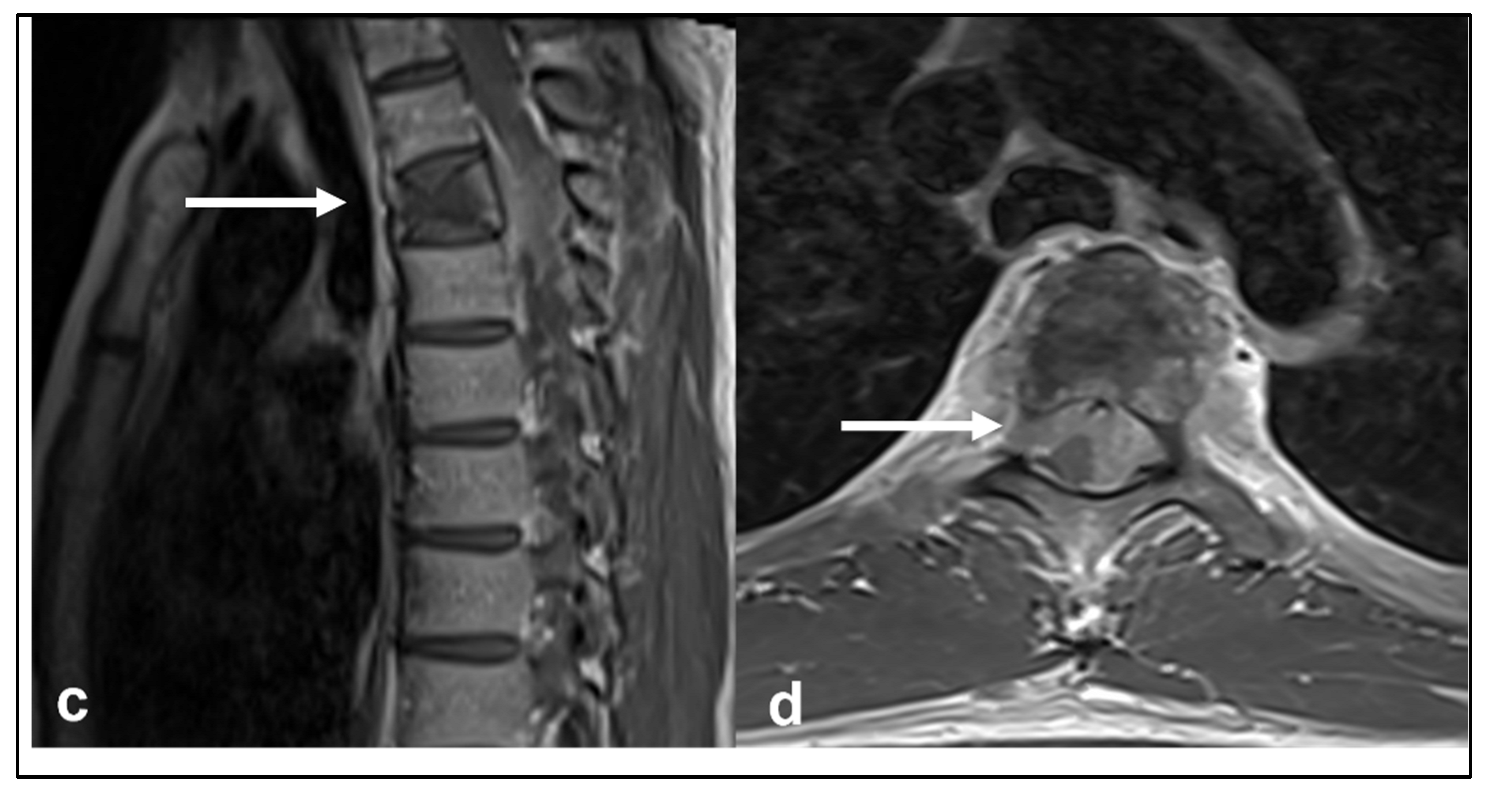

3.2. Ewing Sarcoma

| Ewing sarcoma | Lytic lesion. Vertebral collapse. | Low to intermediate signal T1 and intermediate to high signal T2 lesion. Enhancing extra-osseous soft tissue component. |